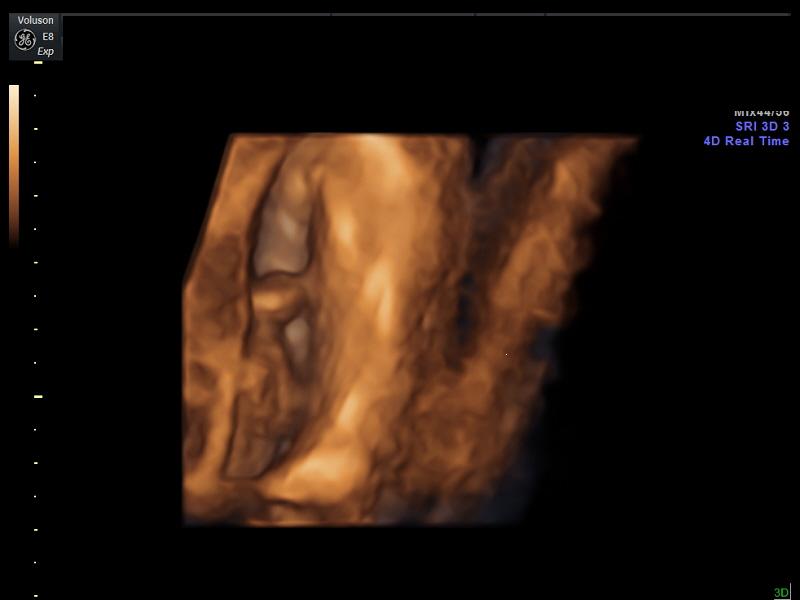

Ahojte babeny tak ako sa vam dneska dari? My sme boli v utorok na poradni, malinka je ok, niektorymi mierami sa predbiehame vraj o dva tyzdne, asi bude dlha po tatovi 🙂 a vazime nieco cez 2,6 kg. Videli sme, ze je vlasata, takze nam vyjde von asi maly pankac. 🙂 A rukou si hladkala ritku, mala uchylacka. 🙂 A inak je vsetko ok, akurat ze ten moj tlak sa im nepozdava, mala som 135/85. No a Dr. sa rozhodla ma poslat na interne vysetrenie - z coho vyplynulo ze nieco ako predoperacne aby som mala keby som nahodou musela ist v nemocnici sekciou. A este mi tam pisala na nefrologiu, ale to neviem ci budem musiet, ci to az podla vysledkov z interneho. Taaaaaak uvidime, ale ja sa citim vyborne a malinka je aktivna a zlatucka. 🙂